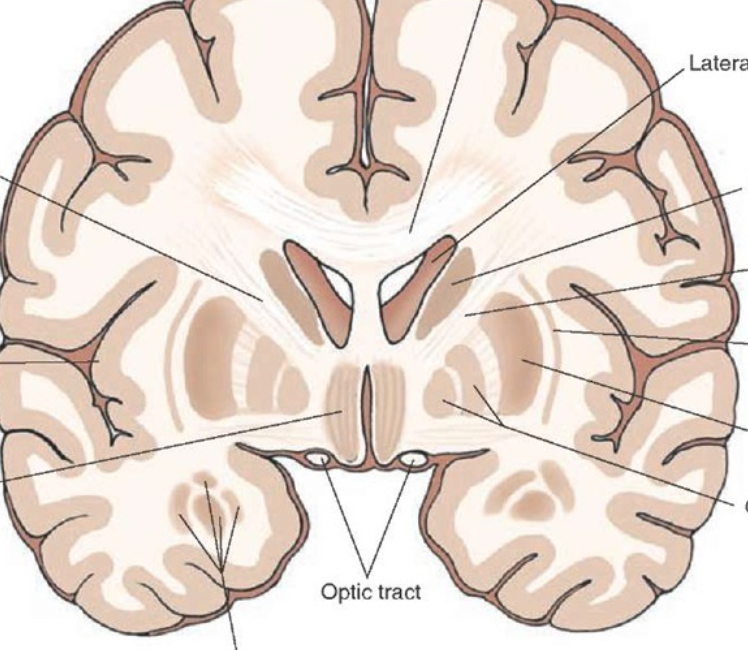

what is the ventricles of the brain?

cavities in brain are known as the brain ventricles, contain choroid plexus, makes a total of 600-700ml of CSF per day

where does CSF circulate before being reabsorbed at the arachnoid granulations?

CSF circulates through the ventricular system and subarachnoid space before being reabsorbed at the arachnoid granulations

what supplies the ventricles with blood?

internal carotid artery